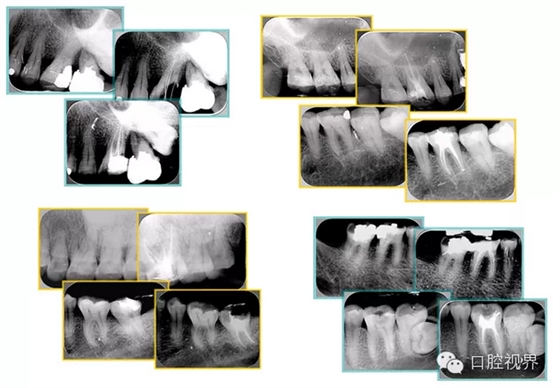

根管預備步驟包括: ( 1 )橡皮障的使用。 ( 2 )X片共四張 (術前、診斷絲 、主牙膠尖確認、術后)。

共有 4 張 X 線片,分別是術前、診斷絲 、主牙膠尖確認、術后。

( 1 )術前:術前 X 線片用來了解牙齒的大概情況。術前預期為多根牙時 X 線片應偏頭拍攝。

( 2 )診斷絲:根據(jù)術前 X 線片進行開髓、根管的初步預備后,需要插入診斷絲,用來指示工作器械位置。常用 10 號或 15 號擴大器作為診斷絲插入牙髓腔。

( 3 )主牙膠尖確認:通過術前預期和診斷絲診斷,明確工作長度、牙根走向,進行根管預備。之后應進行主牙膠尖(中銼)確認,已明確根管是否適合充填。

( 4 )術后:觀察治療效果。